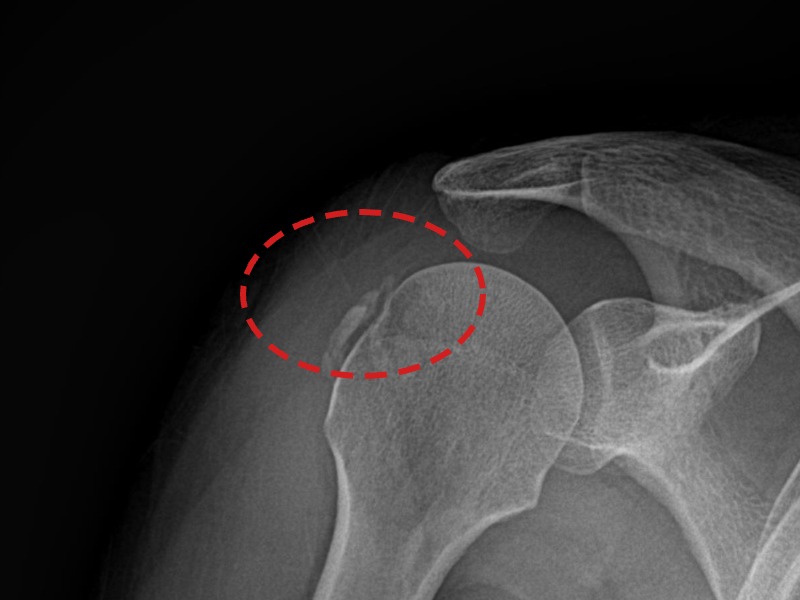

[촬영시기:21.09.02~21.10.07]

[석회분쇄흡입술] 좌측 어깨 통증으로 팔을 옆으로 올리기 어려워진 60대 남성 환자로, X-ray에서 좌측 극상근건 내 석회 침착이 확인되어 석회분쇄흡입술을 시행하였습니다.